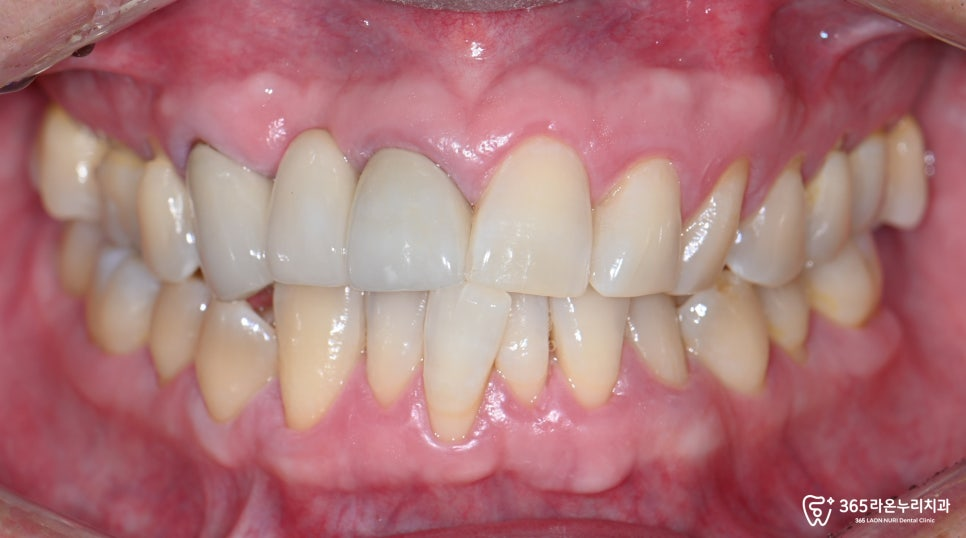

우선 전체적인 구강의 상태를

확인해볼 필요가 있습니다.

엑스레이에선 보이지 않지만

왼쪽 두 번째 앞니 안쪽(구개면)으로

우식이 관찰되고 있었습니다.

그리고 오른쪽 아래 어금니 교합면에도

거뭇한 우식이 관찰되었는데요.